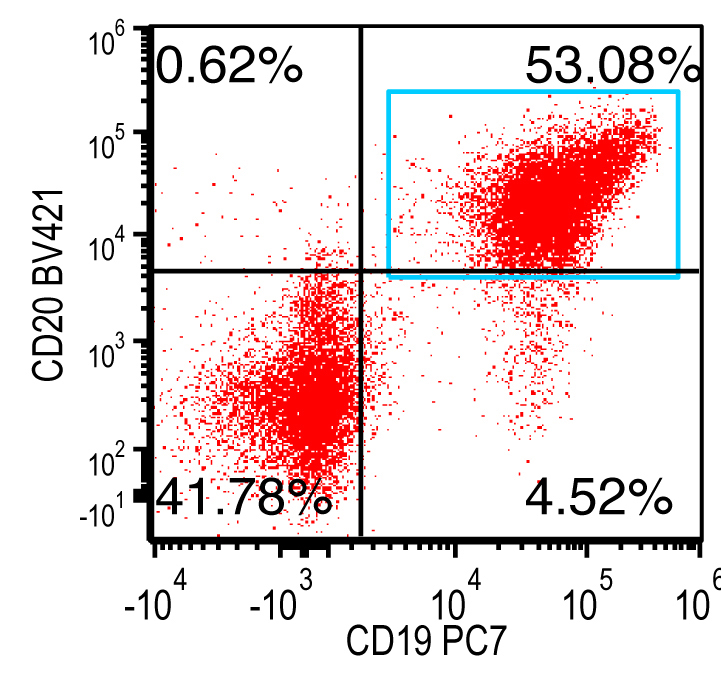

- Flow cytometry: monoclonal B cells with typical immunophenotype and monoclonal plasma cells

- Immunophenotype of LPL cells: IgM+, CD19+, CD20+, CD22+, CD25+, CD10-, CD23-, CD103-, variable CD138

- Immunophenotype

- Positive: IgM, CD19, CD20, CD22, CD79a, CD25 and CD38 frequent expression

- Negative: CD5, CD10, CD103, CD23; however, CD23 expression is not uncommon in some cases

Flow cytometry description

Flow cytometry images

Contributed by Ling Zhang, M.D. and Caroline An, M.D.